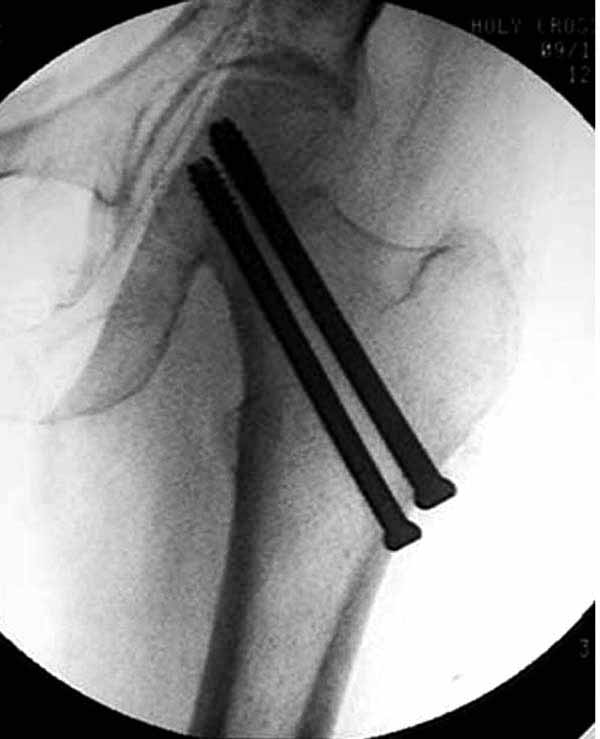

Как отметили коллеги, необходимо обратить внимание на последовательность введения каннюлированных шурупов. Рекомендуется введение в форме “V”, т.е основанием вниз, потому что в другой последовательности за счет увеличения стресса латерального кортекса имеется риск перелома. За редким исключением удается установить Guide wire с первой попытки и многоразовые пробы спицей увеличивают стресс. Небольшая травма может привести к перелому.

Работа Burstein AH and Wright TM: Fundamentals of Orthopaedic Biomechanics. Williams & Wilkins, Baltimore, pp. 160-169, 1994 доказывает, что шурупы, введенные на уровне малого вертела или ниже, приводят к осложнению. Введенные шурупы под 135 и больше градусов в 20% осложнились подвертельными переломами бедра.

Здесь подобный случай, где стрессовый перелом обнаружен через 2 недели после фиксации. Применен Blade Plate с дополнительными шурупами.